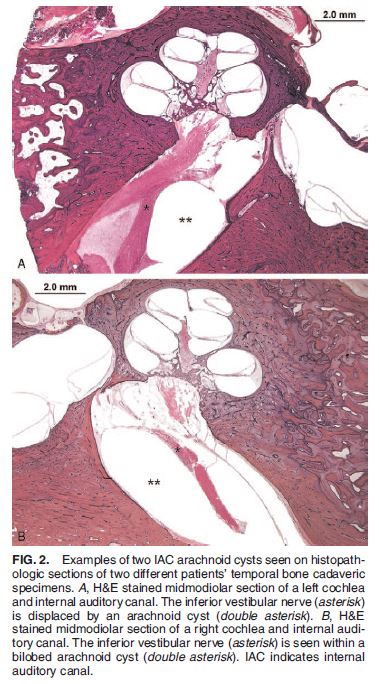

A rare, or possibly rarely described, entity not to forget when an MR seems 'negative' for SNHL, esp if there's history of trauma. Follow CN VIII in the IAC on hT2W seq, see if there might be a focal deviation that might just be a tiny IAC arachnoid cyst! pubmed.ncbi.nlm.nih.gov/34999615/

A rare, or possibly rarely described, entity not to forget when an MR seems 'negative' for SNHL, esp if there's history of trauma. Follow CN VIII in the IAC on hT2W seq, see if there might be a focal deviation that might just be a tiny IAC arachnoid cyst!

pubmed.ncbi.nlm.nih.gov/34999615/